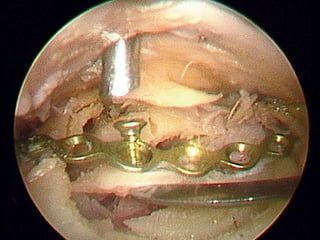

• #16 Endoscopic brow-lifting instruments have also been adapted for those that which a coronal incision might seem be excessiveThe OR field is viewedendoscopically. ORIF is done percutaneously. This approach is suitable & limited to anterior table fractures.

• #17 Management of the internal frontal sinus requires removal of the anterior table, through elevation of fractured segments or though osteotomies of intact segments. Ideally, periosteal attachments are maintained but is not necessary for the survival of the bigger bone fragments. Smaller fragments can be replaced by bone grafts.